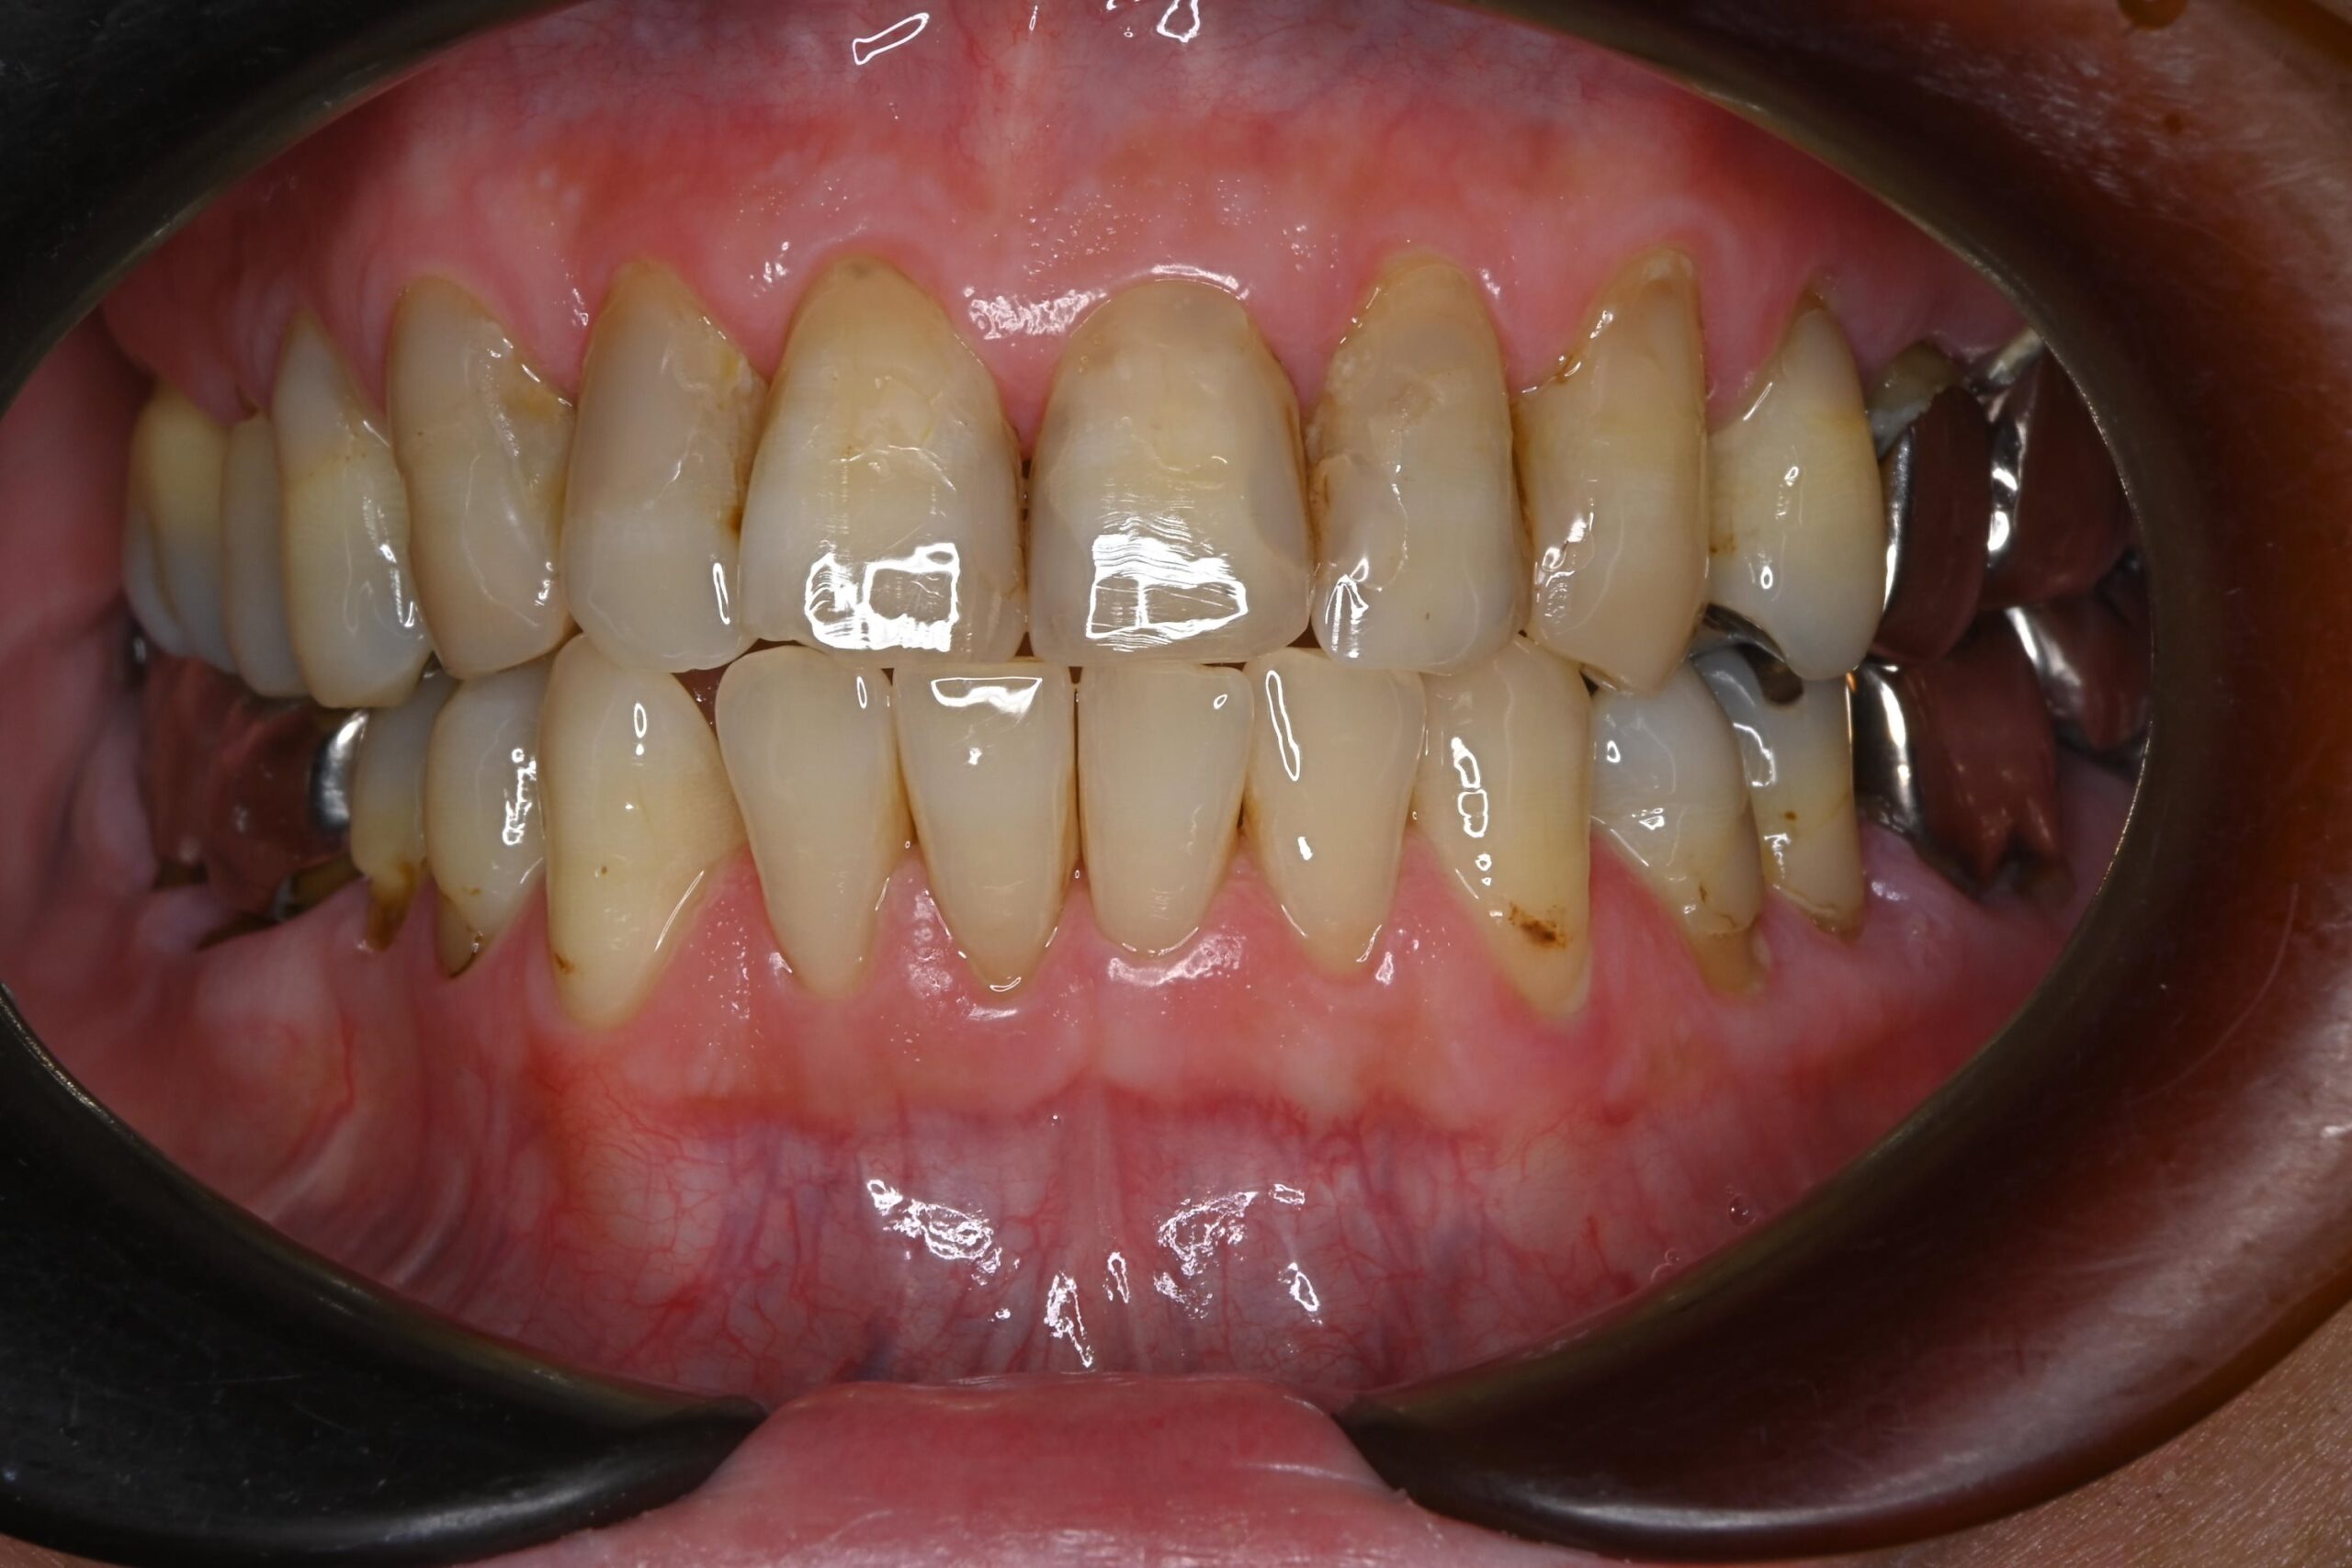

治療結果

銀歯をすべてセラミックへ置き換え、あわせてホワイトニングを行ったことで、口腔内全体が明るく清潔感のあるお口元になりました。また審美的な向上が得られただけでなく、プラーク(細菌)が付着しにくい環境を整えることができた点も大きな成果です。

また、痛みや違和感の原因となっていた部位についても適切な処置を行ったことで、現在は違和感なく、安心して噛める状態が維持されています。

機能面と審美面の両面において、良好な治療結果が得られました。

After